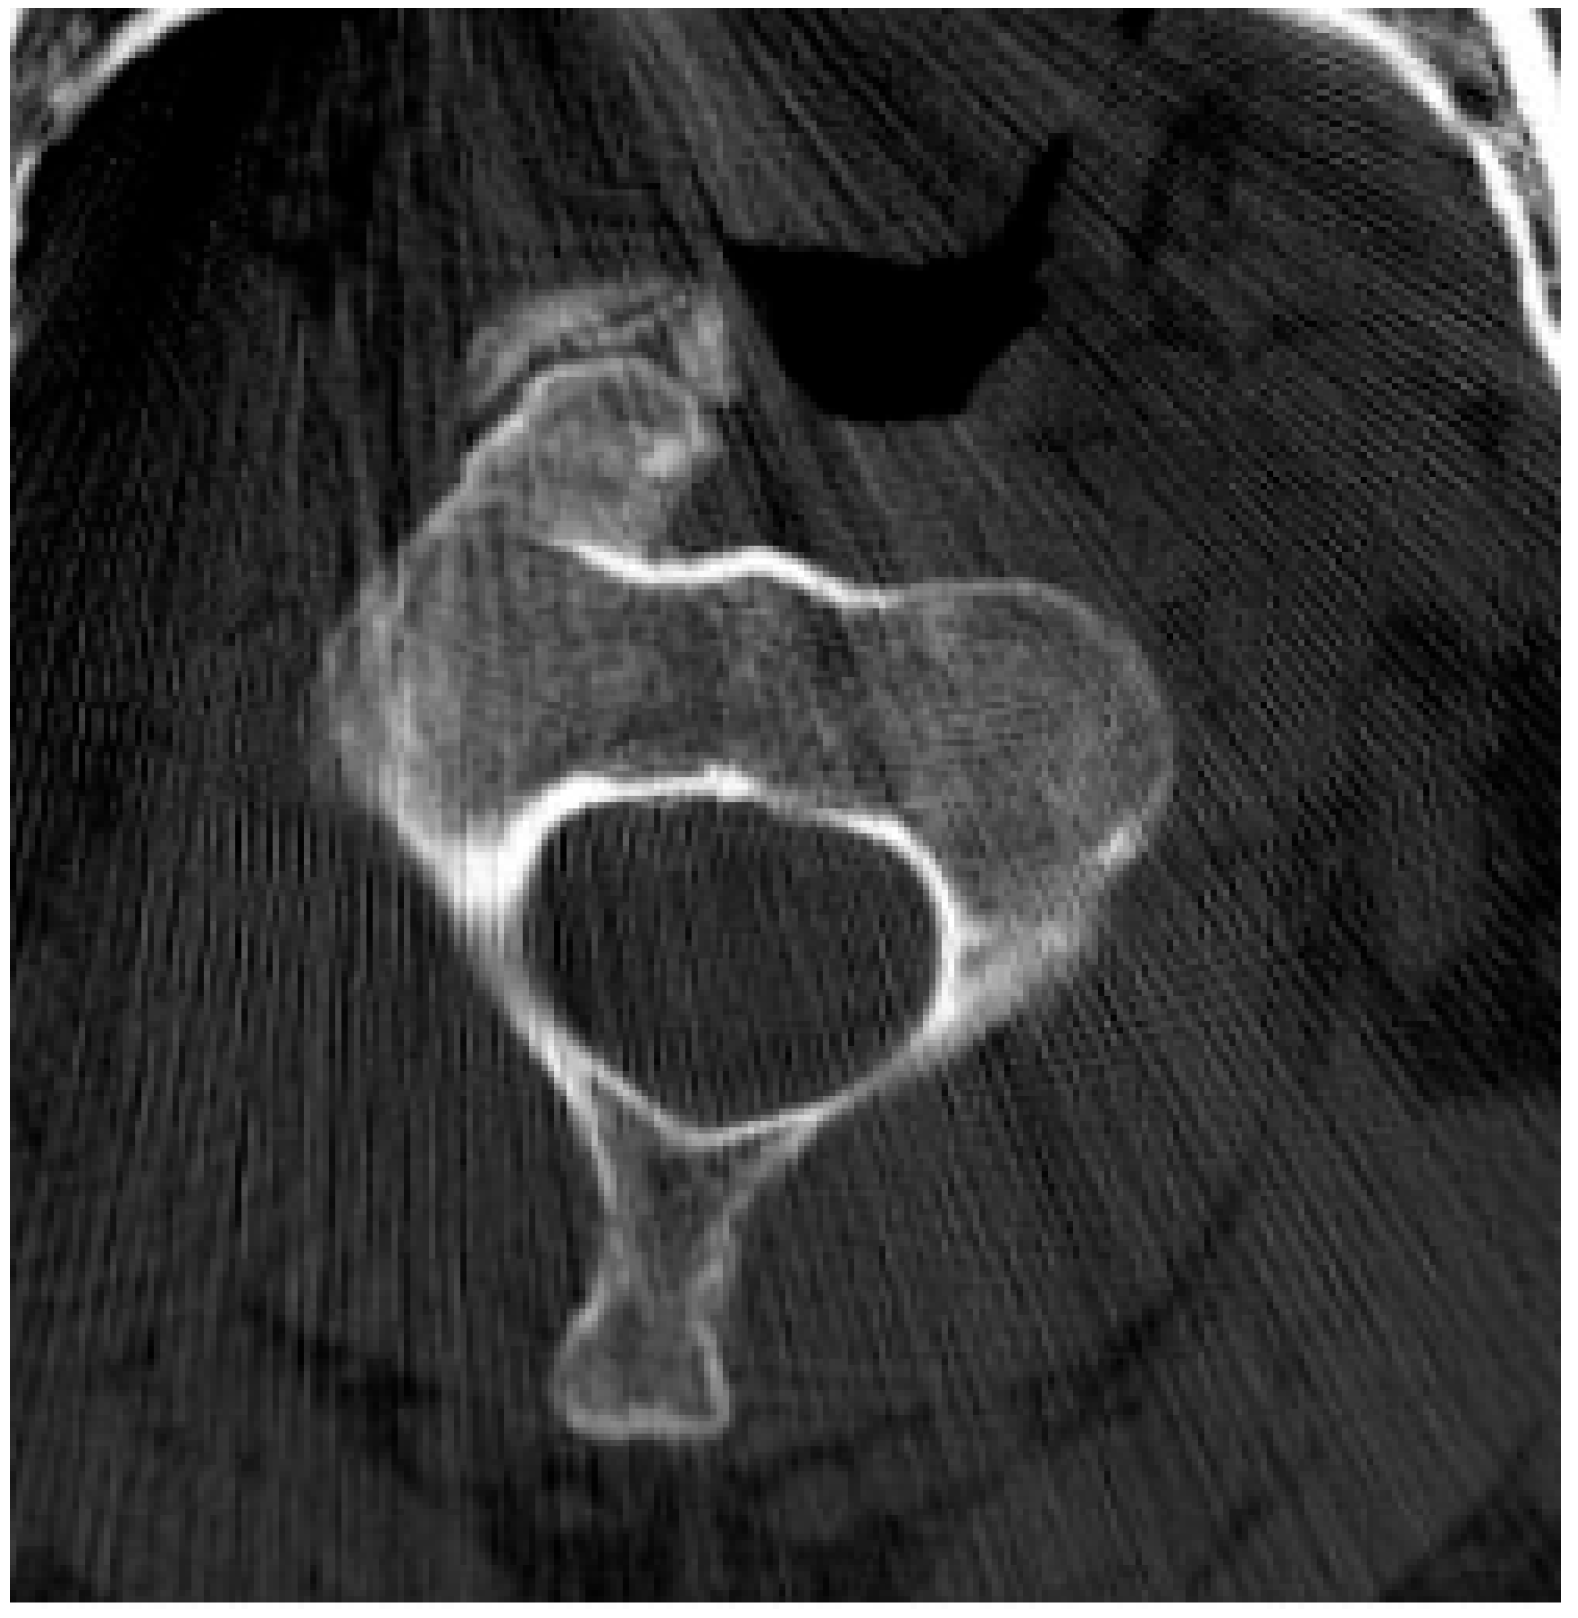

2.5.2. Aneurysmal Bone Cyst

2.6. Fibro-Osseous